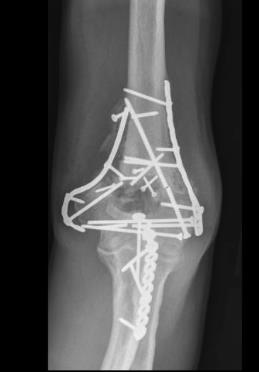

Tibial Plafond Fractures

Ankle Fractures